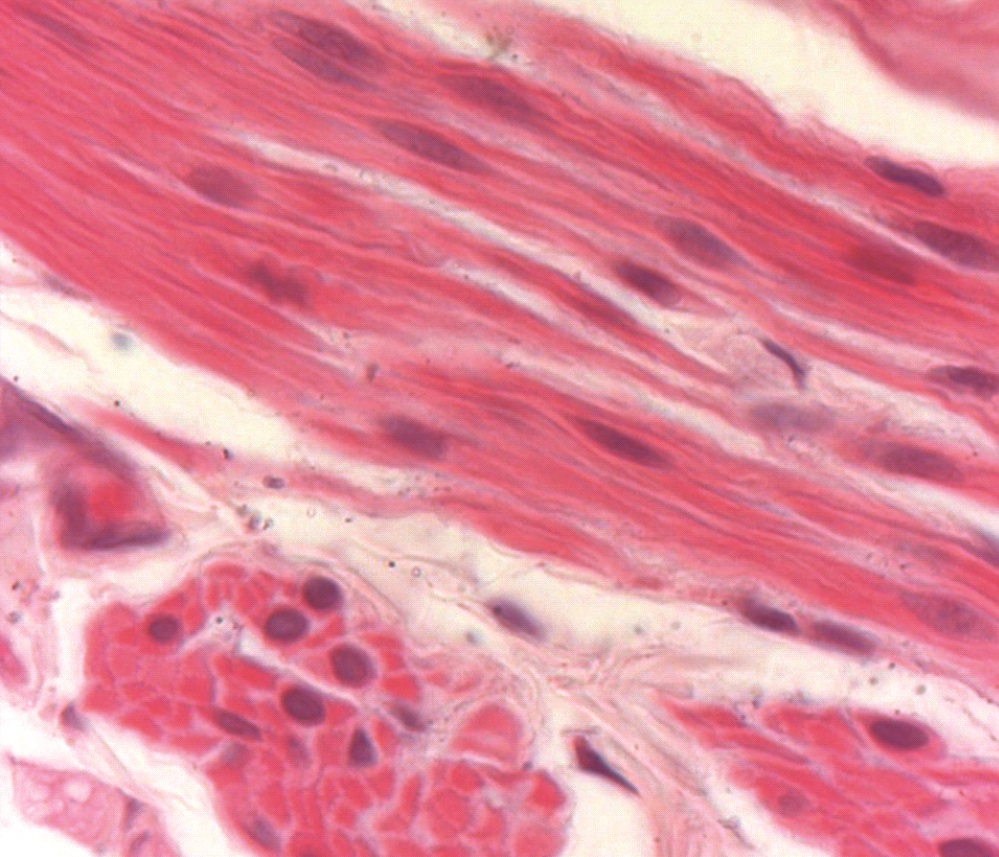

В течение первых суток в раневой зоне развивается интерстициальный отек без признаков воспалительной реакции. Зона отека расширяется до седьмых суток после начала эксперимента. В результате нарушается интеграция миоцитов. Это обнаруживается светооптически в виде расхождения клеток (рисунок 1), вследствие чего наблюдается полная или частичная дезинтеграция небольших групп или отдельных гладких миоцитов. Лишь отдельные группы миоцитов сохраняют взаимодействие и остаются жизнеспособными.

Рисунок 1. Гладкая мышечная ткань внутреннего сфинктера прямой кишки. 24 часа после перерастяжения. Нарушен контакт между миоцитами, начинается отек интерстиция. Окр. Г.+Э. Об. 100. Ок. 15.

Figure 1. Smooth muscle tissue of the internal anal sphincter. 24 hours after overstretching. Contact between myocytes is broken, interstitium edema begins. Staining with hematoxylin and eosin. Ob. 100, oc. 15.